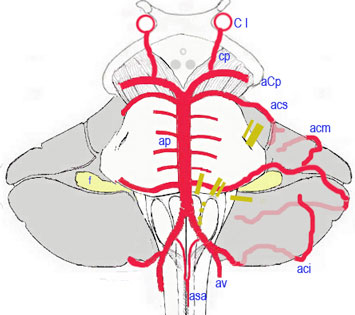

Polygone de Willis trac autour du losange opto-pdonculaire

Aspect ventral du tronc crbral et du losange opto-pdonculaire

-aci: artre crbelleuse postro-inf.

-acm: artre crbelleuse moy.

-acp: artre crbrale post.

-acs: artre crbelleuse sup.

-ap: artres pontiques

-asa:artre spinale ant.

-av: artre vertbrale

-ci: carotide interne

-cp: communicante post.

Le tronc basilaire constitue son unique terminale, il rsulte de la confluence des deux artres vertbrales la hauteur du trou borgne. Cest un tronc mdian et impair de 3 cm de long, il chemine entre la gouttire basilaire de la protubrance et lapophyse basilaire de loccipital; il se termine la hauteur du sommet de lespace perfor postrieur en bifurquant en deux branches terminales, les artres crb­rales postrieures qui prennent part la constitution du polygone de Willis.

Auparavant, il distribue des rameaux

- la protubrance,

- au bulbe (artre de la fossette latrale )

- au nerf auditif (artre labyrinthique), et

- au cervelet (artres crbelleuses infrieures et moyenne).